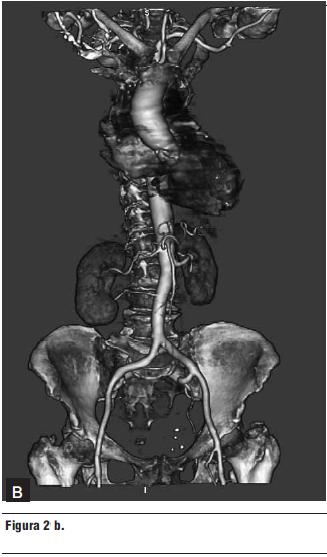

2. Tomografía computada multicorte (16 líneas) (figura 2 a y b).

- Válvula aórtica intensamente calcificada.

- Calcificación del anillo mitral.

- Múltiples placas calcificadas en la aorta torácica.

- Arterias ilíacas de buen diámetro, sin bucles.

- Diámetro de la arteria femoral derecha: 9,3 mm.

- Diámetro de la arteria femoral izquierda: 8,1 mm.